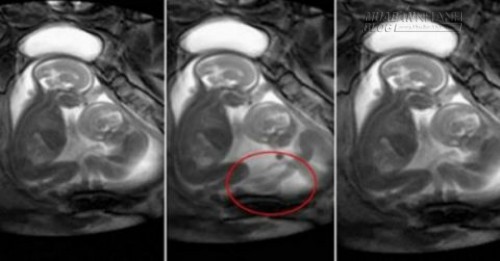

Em bé ở dưới đang dùng chân đẩy người anh em

Đoạn video của Trung tâm chăm sóc thai nhi London lại "dậy sóng" khi được các bà mẹ chia sẻ nhiều trong thời gian gần đây. Những hình ảnh cặp song sinh đang "chành chọe" nhau để giành không gian cho mình ngay trong bụng mẹ đã khiến người xem thích thú. Cảnh "xung đột" đáng yêu này được ghi lại bằng thiết bị MRI trong quá trình bác sĩ chụp chiếu để chẩn đoán căn bệnh hiếm gặp là hội chứng truyền máu song thai. Tuy nhiên, hầu như các bố mẹ khi xem đoạn video này đều chú tâm tới những cử chỉ của hai em bé, cách em bé phía dưới dùng chân đẩy người anh em của mình và em bé ở trên mấp máy miệng như thể đang phàn nàn một điều gì đó.